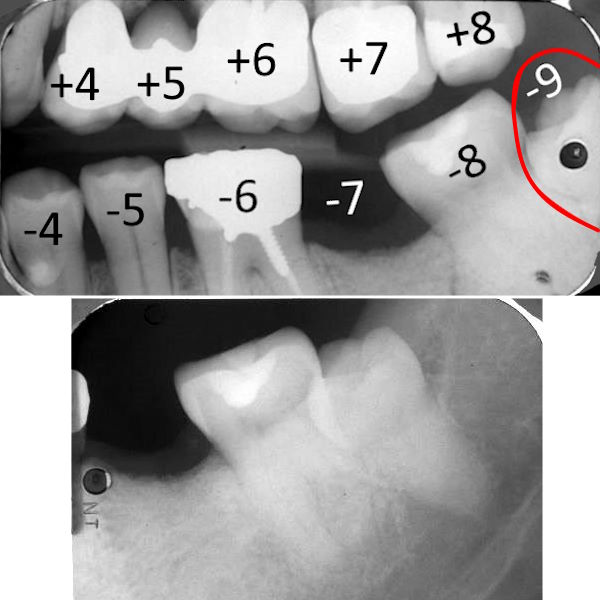

24-jähriger Patient (30.08.2018 / 3486)

Dieser Patient hat insgesamt 6 Zwergzähne, nämlich

8+7 und 75-57.

24-jähriger Patient (20.11.2023 / 4935)

Beide oberen Weisheitszähne haben eine komische Form.

Einer hat in kurzer Zeit wie von selber eine tiefe Karies bis zum Nerv bekommen.

Alle anderen Zähne haben noch nie Karies bekommen.